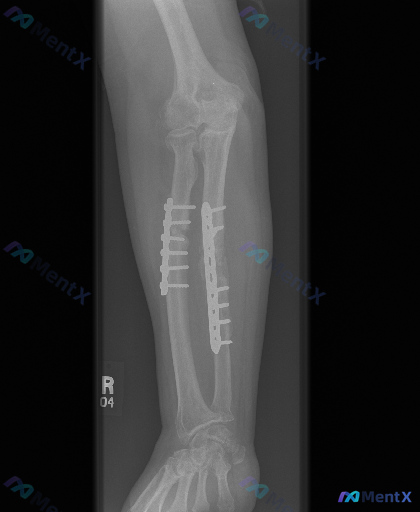

这张右侧前臂侧位X光片,你会如何解读核心发现?

整理到一张右侧前臂的侧位X光片资料,读片发现如下表现:

- 尺骨和桡骨骨干部位均有金属钢板及螺钉内固定

- 骨折断端可见骨痂生长,骨折线模糊

- 肘关节、腕关节对位关系大致正常,未见明显脱位

- 软组织轮廓清晰,无严重肿胀或皮下气体影

- 未见明显骨质疏松或溶骨性破坏,骨骺线已闭合

📋答案:右侧前臂尺桡骨双骨折术后(愈合期)